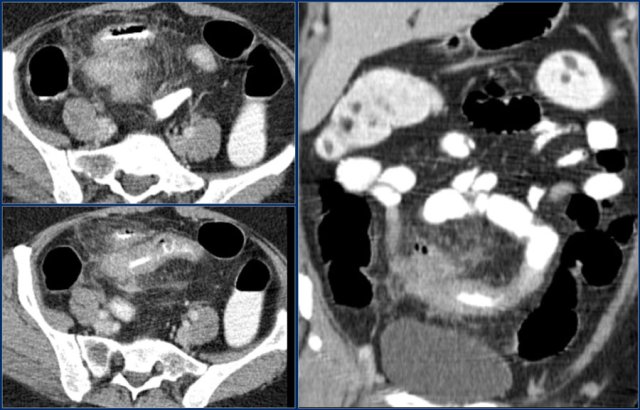

Here a patient with metastatic melanoma.

Left image shows ileal-ileal intussusception due to metastasis.

Right image shows intussusception in coronal plane as well as an enlarged mesenteric lymph node (yellow arrow) and extensive liver metastases.